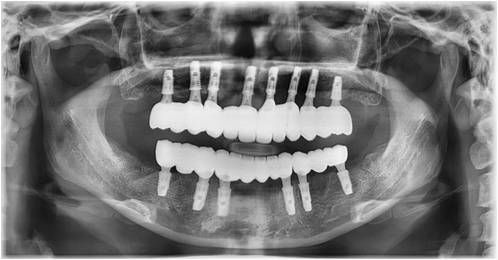

치주질환이 심해졌거나 나이가 들면서 잇몸상태가 안 좋아져 치아를 받치고 있는 치조골이 많이 소실되면 치아가 흔들립니다.

이때 치아가 얼마 남아있지 않아 틀니와 임플란트를 고려하게 되는데 틀니는 잇몸 위에 얹는 방식이라 씹을 때 잇몸에 압박이 가해지고

제대로 힘들 받기 어려운 점이 있다면 임플란트는 식립을 하여 사용하기 때문에 자연치아만큼 편안한 사용이 가능합니다.

전체 임플란트의 대상자는 주로 고령자입니다.

때문에 전신상태인 건강, 당뇨 등 수술에 영향을 주는 질환 유무를 파악하고

전문의와 상담을 통해 진행 유무를 확인하시는 것이 중요합니다.